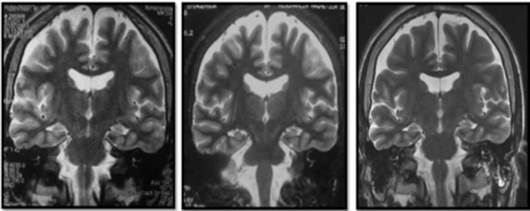

Cerebral nuclear magnetic resonance (NMR) showed generalized cortical atrophy and bilateral hippocampal atrophy (Figure 1), while electroencephalogram revealed independent bilateral temporal ictal activity, frequently associated with bradycardia and hypoxemia (Figure 2).

With respect to neuroimaging, the variations observed in the MRI range between normal findings and different degrees of atrophy and hyperintensities in the temporal lobe, mainly in the hippocampal region 12,25,26, as well as in the insula and basal ganglia 11, perhaps secondary to prolonged neuronal activation 4.